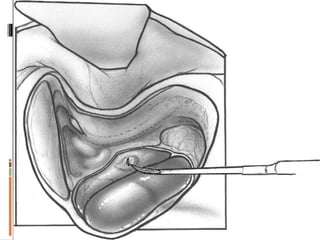

 Sacculotomy (Ficks operation)….Cody tack

COCHLEOSACCULOTOMY

Selection criteria

 Severe vertigo

 Tumarkin crisis

 BEST for Old patients unable to tolerate GA

 EASYTO PERFORM

 ALMOST FREE FROM MORBIDITY

 NO POST OPERATIVEVERTIGO

 Hearing preserving

Sometime drill lip

Hug the lateral wall

Feeling of give way

complications

 Similar to stapedectomy